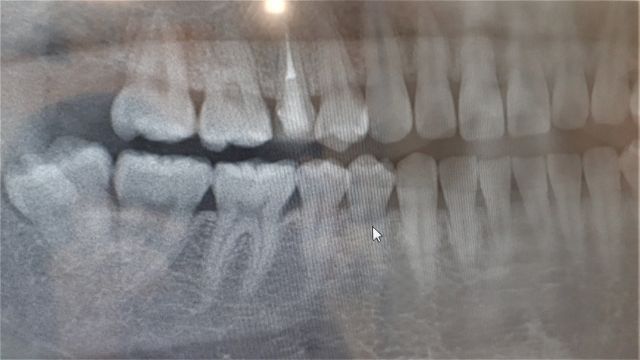

レントゲン写真で、親知らずの生え方(萌出状態)、歯根の状態、周囲の組織との関係などを確認します。レントゲンを見てみると、完全に埋まっている・歯茎に埋まっている部分だけ炎症を起こしている・隣の歯を押しているなど、さまざまなケースがあります。

これらの状態を正確に把握することが、抜歯の必要性を判断する第一歩です。

また、完全に見えない状態の親知らずも歯茎の下で虫歯や歯周病になっていたり、将来的になるかの可能性が高い事もあるため、レントゲンで位置を確認し前述の様な状態の場合は抜歯が推奨されます。

また、レントゲン写真だけでなく、口腔内の状態、痛みや腫れなどの症状、そして年齢や全身状態も考慮され、抜歯の判断をします。